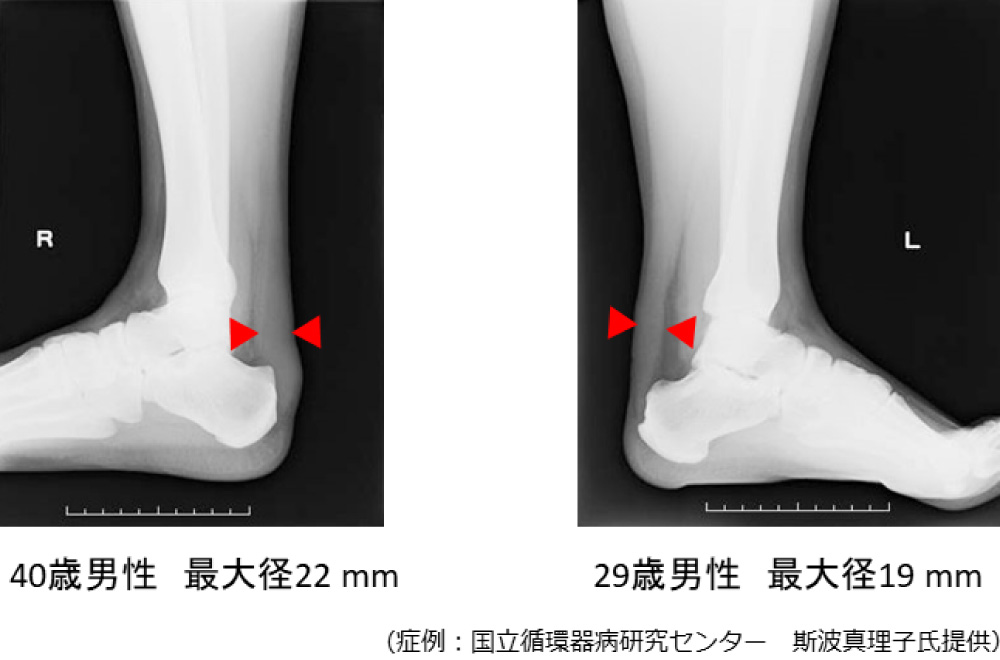

※腱黄色腫の存在は、アキレス腱X線軟線撮影により、男性8.0mm以上、女性7.5mm以上で診断する。あるいは超音波検査により、男性6.0mm以上、女性5.5mm以上にて診断する。

FHにおけるアキレス腱X線撮影

出典:日本動脈硬化学会(編):成人家族性高コレステロール血症診療ガイドラインフォーカスアップデート2025 日本動脈硬化学会,2025